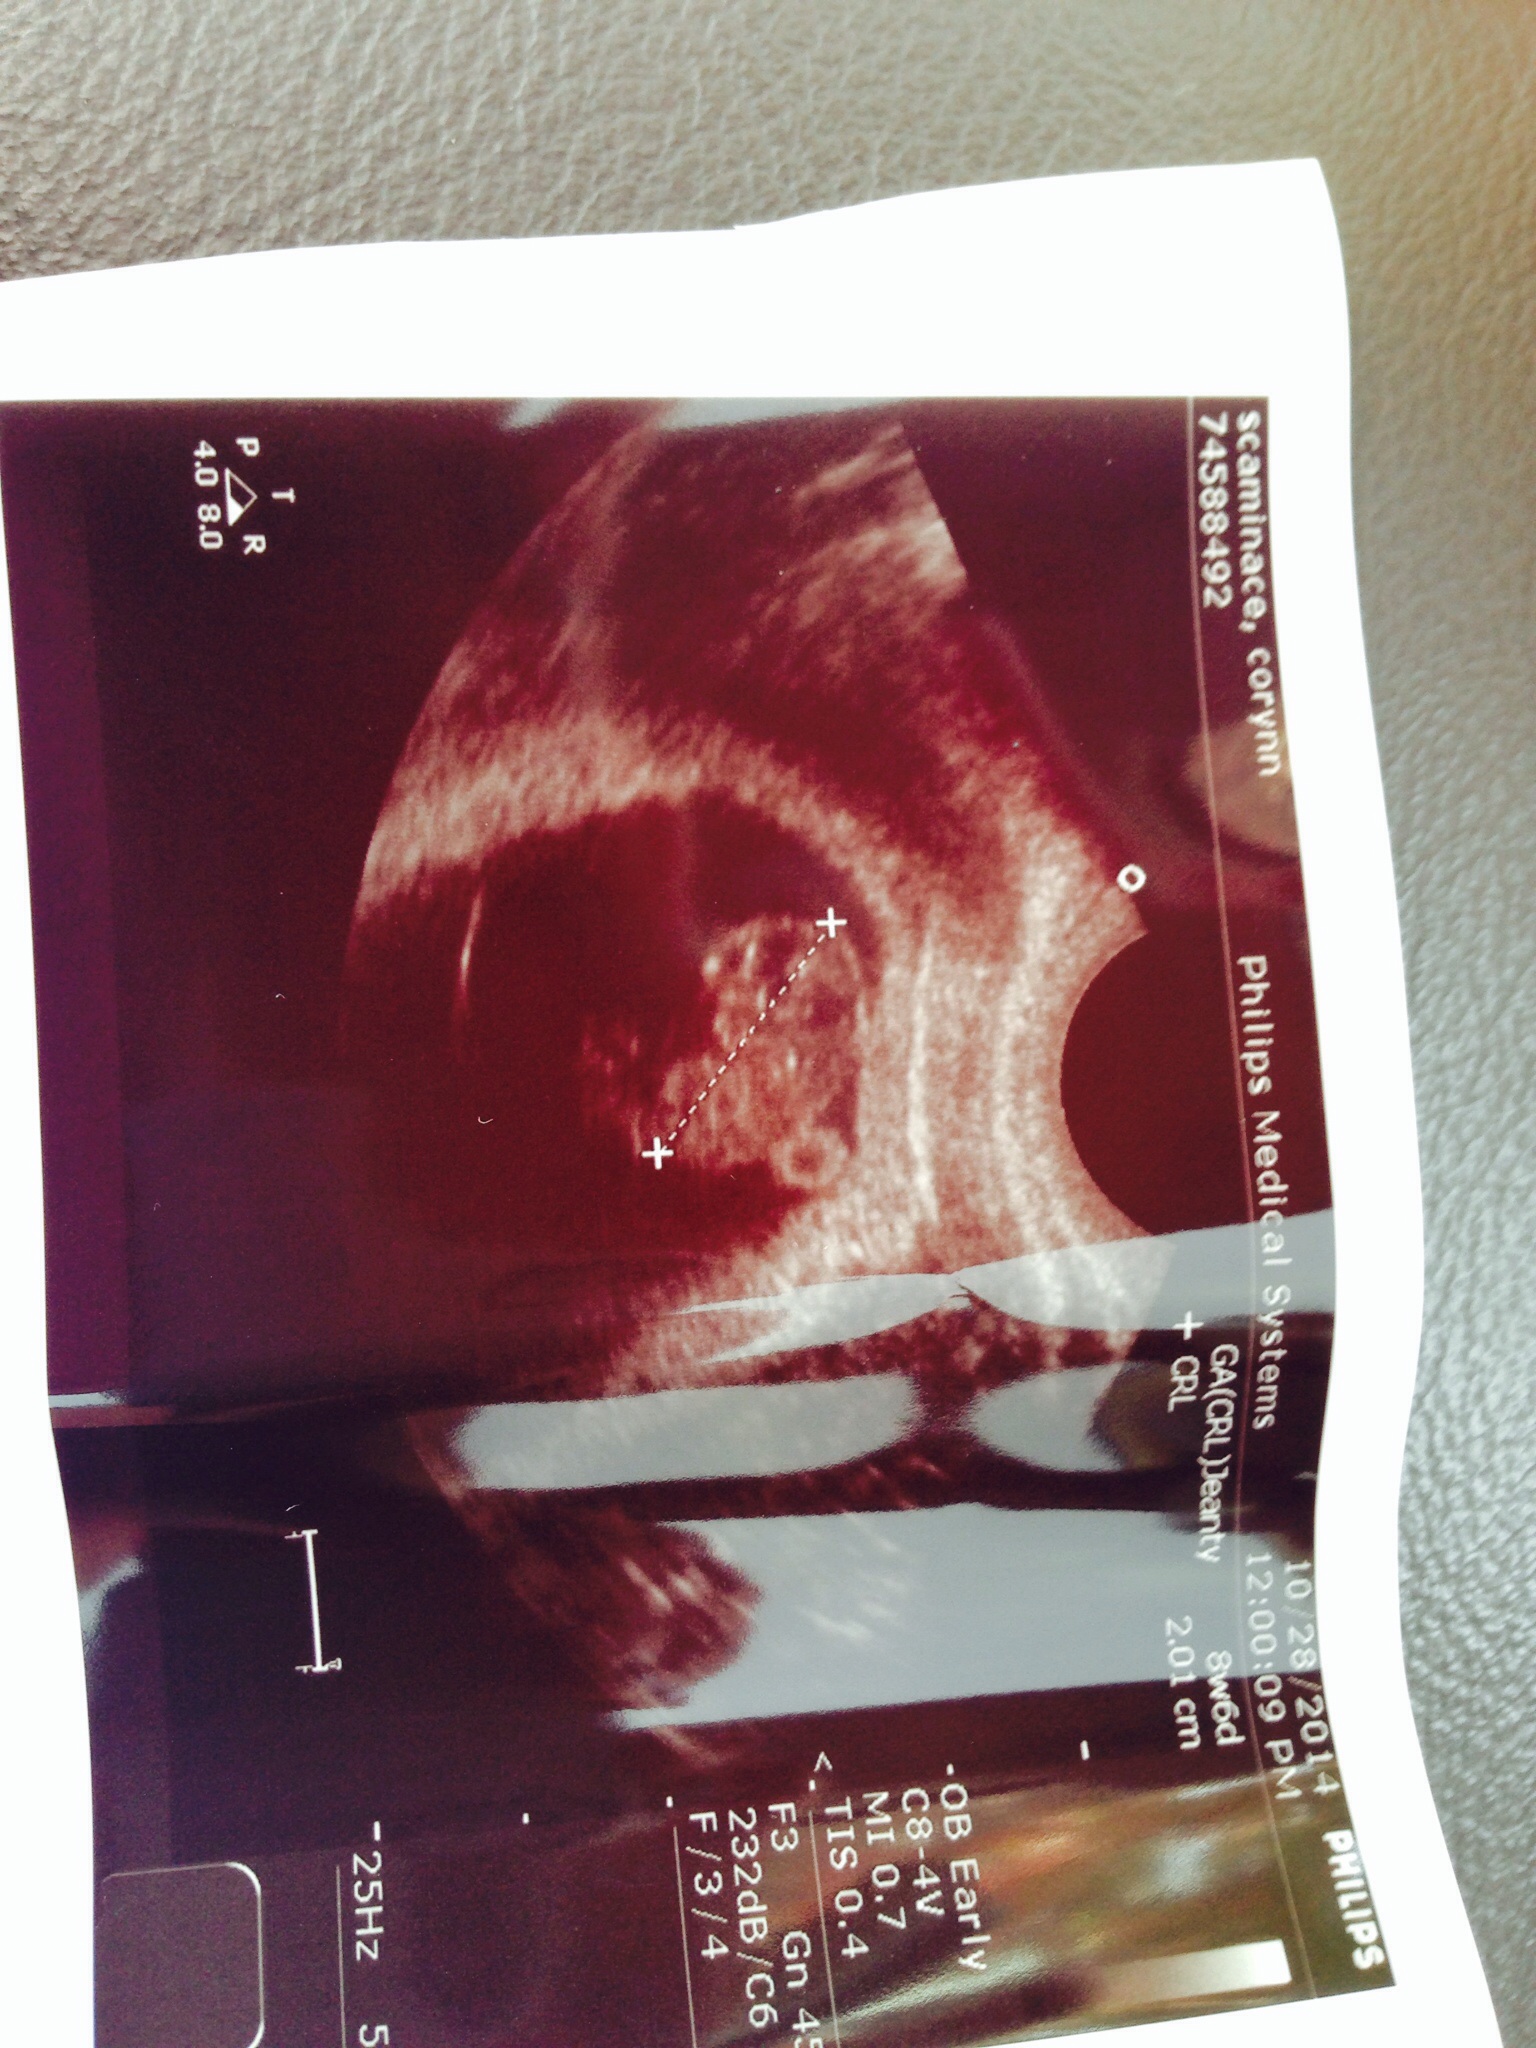

This is mine, went in 10-22 for an 8 week appointment (Kaiser Permanente insurance) turned out to be 7 weeks so I have to go back in for an "official" US on 11-3, but they still gave me a printout of my little McNugget! Seeing the heartbeat on the screen was my light bulb; I suffer from a chronic illness that makes me experience constant nausea, stomach pain and exhaustion (basically preggo without the fun prize in 9 months) so I didn't "feel" pregnant. Watching that flutter, it finally sank in.